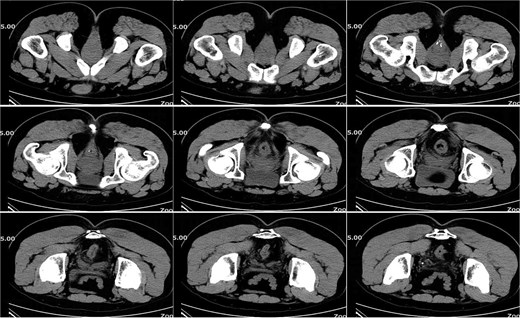

On postoperative Day 7, the patient developed a fever (38.5°C) and mild lower abdominal discomfort. Laboratory tests revealed leukocytosis (white blood cell count: 16.06 × 109/l, neutrophil percentage: 89.1%). A pelvic computed tomography (CT) scan suggested cystitis (Fig. 1). Anti-infective therapy with intravenous cefoperazone sodium and sulbactam sodium was initiated. The patient’s vital signs, complete blood count, and temperature were closely monitored.